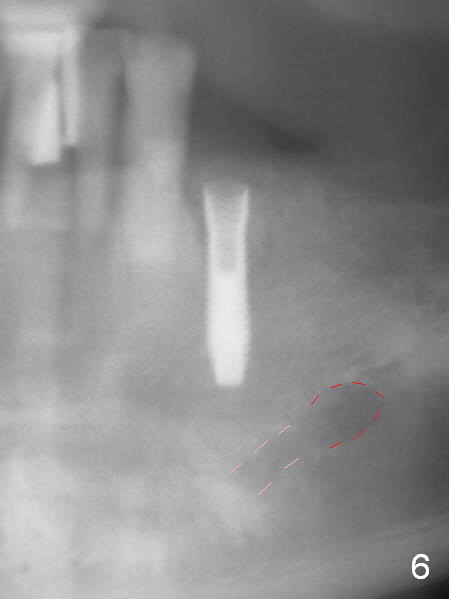

A 72-year-old man presents to clinic for implants because of pain associated with wearing the lower partial. The teeth #21, 24, 25 and 31 seem to be non-salvageable and are going to be replaced by implants so that the lower RPD can be reused (Fig.1). The edentulous ridge is atrophic (Fig.9 *). The upper complete denture appears to be functional. Since the tooth #21 is symptomatic (Fig.2) and the patient has chronic TMJ dislocation, the affected tooth is extracted first (Without antibiotic socket treatment) for immediate implant (Fig.3 (1.5 mm drill (placed more lingually)). The lower RPD is used as a surgical guide (Fig.4 (3 mm drill in place)). When a 3.8x16 mm implant is placed with bone graft (Fig.5 *), the underlying neurovascular bundle is undetected. A small field of panoramic X-ray is retaken; it seems that there is enough clearance from the Mental Foramen (Fig.2,6,7 (red dashed line)) and the Incisive Canal (pink dashed line). The implant is then placed 2 mm more apically (Fig.7) to reduce the chance of periimplantitis since the buccal plate is lost. A 5.5x5(5) mm abutment is placed (Fig.5) with more graft. The access of the abutment is left open so that a part of periodontal dressing is inserted for additional retention (Fig.8,9). The RPD is placed back for adaptation of the dressing. The patient is advised not to wear the RPD postop to reduce micromovement.

The patient returns 2 days postop because of hemorrhage (Fig.10,11 * after removal of loose periodontal dressing). Periodontal dressing is repacked (Fig.12). The hemorrhage may be due to incomplete removal of granulation tissue or invasion of the Incisive vessel intraoperatively, although there is no pain or paresthesia postop. Soft food is recommended without the upper complete denture. A provisional is fabricated (Fig.14 P) nearly 3 months postop (after changing the 5.5x5(5) mm abutment to 4.5x5(4) mm, Fig.13) when an implant is being place is #31.